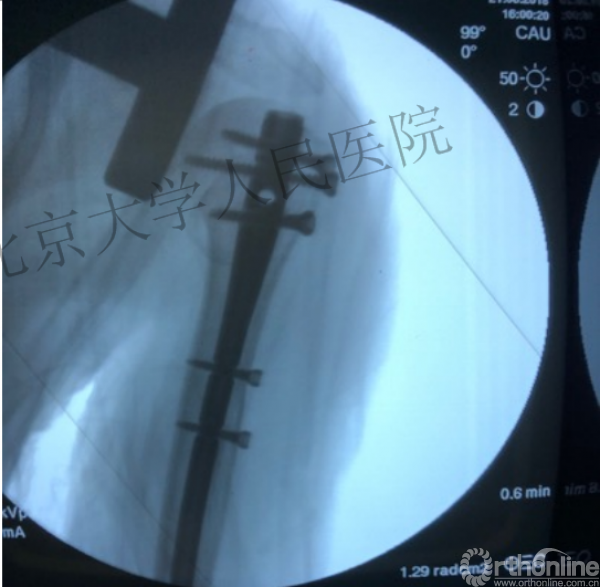

1.体位与C臂机的应用

透视肱骨头正位、侧位确定进针点

复位良好的标准:颈干角:135°,大结节与肱骨头距离:8mm

术中片